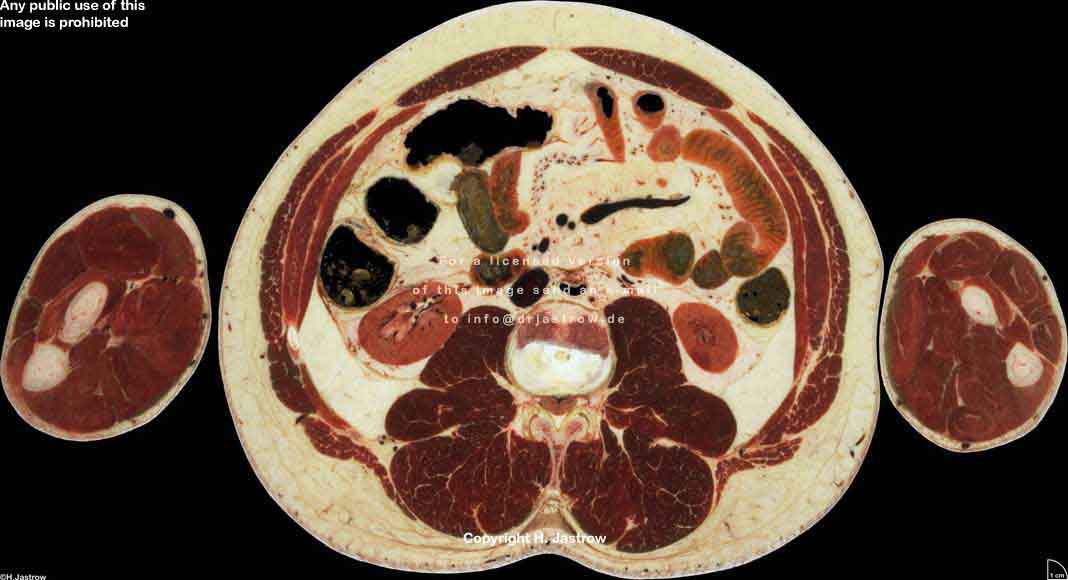

Visible Human male: Sectio transversalis 1657

CT

NMR

Pd                          / T2 \                         T1